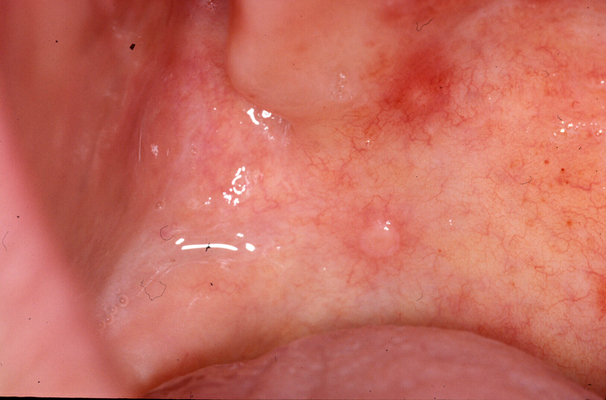

手足口病圖片